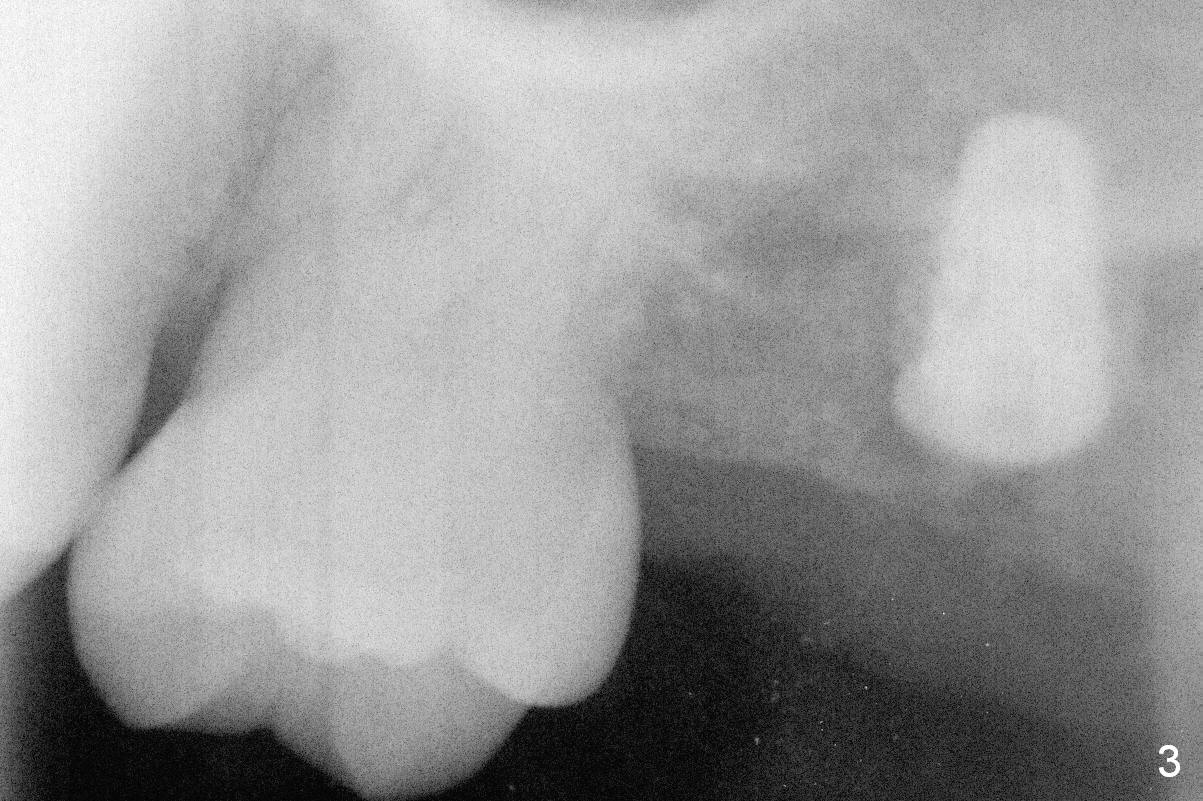

Initial osteotomy at the site of #15 for 4x11 mm dummy implant is created by #15 blade, Magic Split and Magic Expanders (ME) 3.0 and 3.8 mm (flapless, Fig.1,2, 4A (blue circle)). The implant is palatally displaced. Release incision confirms the deviation. A new osteotomy is established with 1.6 mm pilot drill in the middle of the site (Fig.4A (occlusal view) red circle). Distal to the new osteotomy is the incompletely healed socket (brown circle). As the osteotomy is enlarged by ME until 4.3 mm and placement of 4.5 and 5.0 mm dummy implant and of 5.5x9 mm definitive one (Fig.3, 4B large red circle), the osteotomy gradually deviates distopalatally. Introspectively, the new osteotomy should have been placed more buccomesially (Fig.4C red circle) so that the final osteotomy may end up normally (Fig.4D large red circle).

Because of unfavorable implant/crown ratio (Fig.3), the implant will be uncovered 6-7 months postop. An angled abutment is expected to correct the distopalatal displacement of the implant. In the meantime orthodontic treatment should start to align the malpositioned anterior teeth before extraction and implantation.